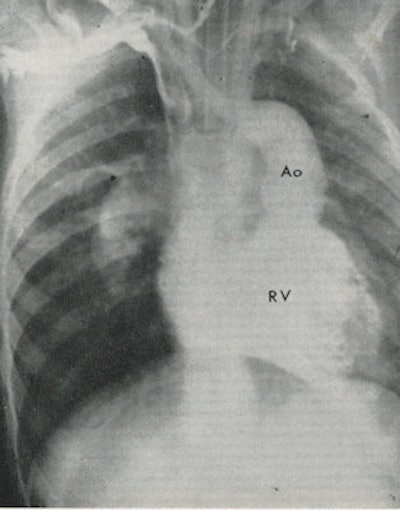

In 1941, Dr. André Cournand and colleagues showed that cardiac catheterization was a safe investigation in humans. Steiner's own interest in angiocardiography started in 1948, when together with Drs. John Goodwin and Sir Edward Wayne, he carried out the first angiocardiographic studies in Sheffield. In 1949, they were the first to demonstrate transposition of the great vessels in a living patient with congenital heart disease.

Steiner showed how advances in radiology profoundly influenced the practice of cardiology so that the cardiologist can correlate clinical findings with hemodynamic and anatomical information found at angiocardiography. He concluded this information has resulted in a more accurate interpretation of clinical findings. This was an exciting time in the history of radiology.